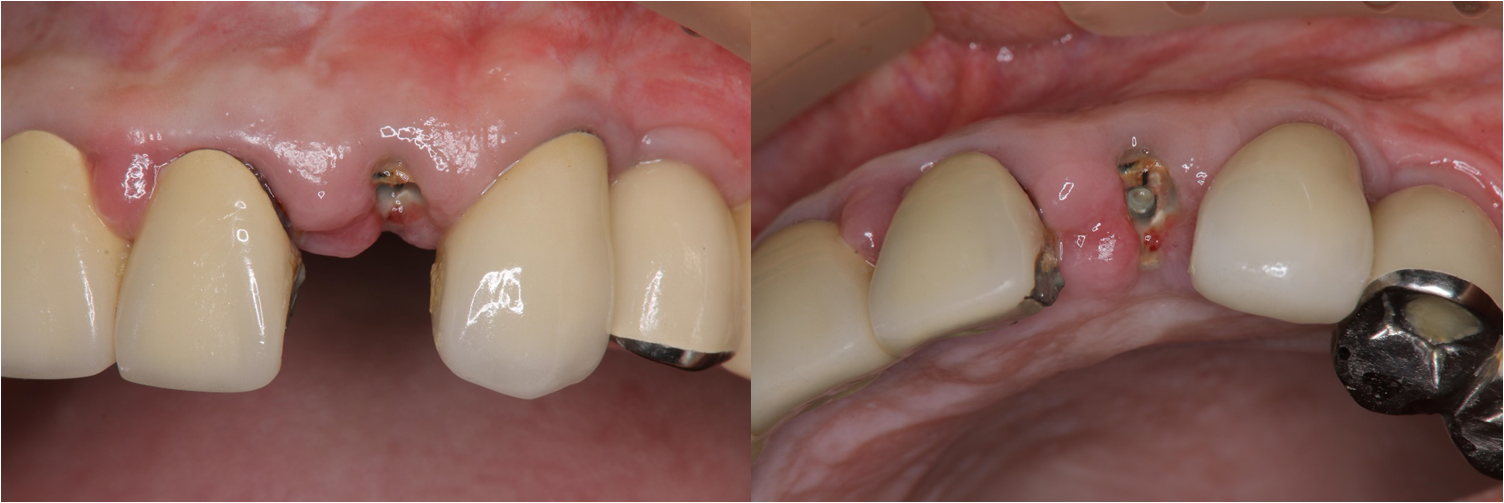

治療前,左上側門齒牙齒斷裂

側門齒之前有做根尖切除,支撐性不足